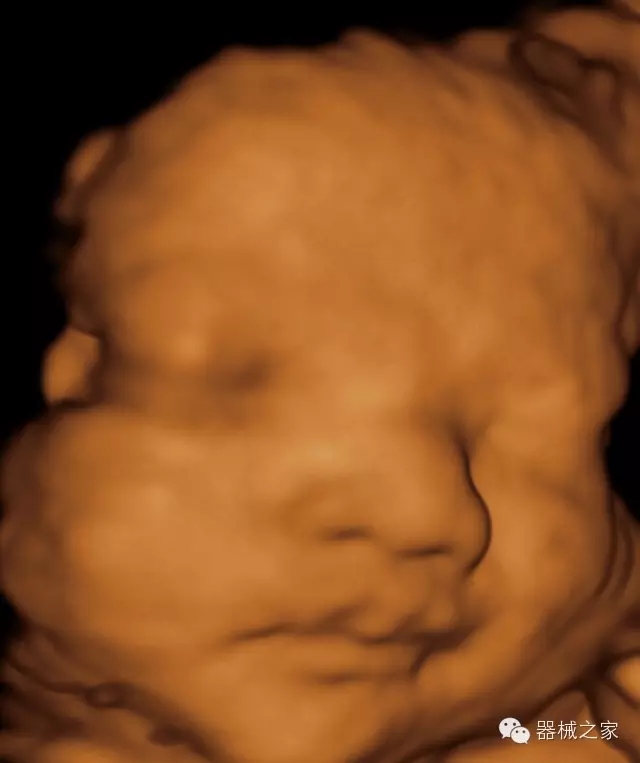

·完整的3D/4D臨床應用,STIC, MCUT 和Auto NT等滿足產(chǎn)科所有應用;

·更高的HQ羊膜腔鏡成像技術(shù)精細觀察每一個暗區(qū)細節(jié);

·高效3D/4D成像技術(shù):高速的4D幀頻,豐富的3D成像模式,智能斷層切片功能;